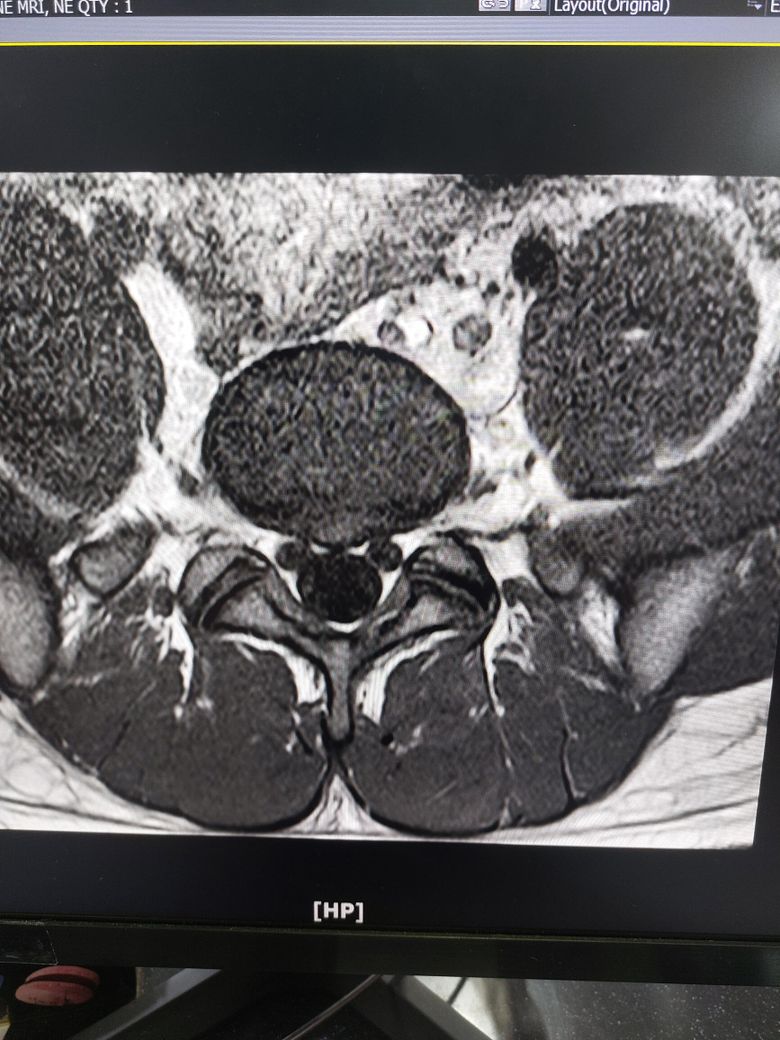

몇개월동안 요추부분이 뻣뻣하고 시큰거려서 (다리 증상은 없음) mri 촬영했는데

디스크 팽윤인가요 아니면 탈출인가요?

증상이 많이 심한가요?

추간판 팽윤입니다

MRI 영상만 가지고 말씀드린다면 심하지 않습니다.

• 올리신 사진 몇 장 가지고 정확한 상태 평가 및 판단을 내릴 수는 없지만 디스크 탈출 보다는 디스크 팽윤이 의심스런 MRI 소견으로 사료됩니다.